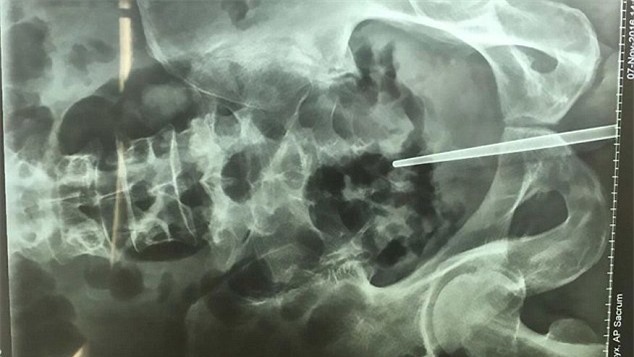

Vì quá lo lắng cho tình trạng đi tiểu ra máu mà ngại không dám đến gặp bác sĩ, người đàn ông này đã tự “khám” bằng cách nhét một chiếc đũa vào trong dương vật của mình.

Người đàn ông họ Trần ở Chiết Giang (Trung Quốc) đã tự khám bệnh tiểu ra máu bằng cách nhét đũa inox vào dương vật thay vì đến gặp bác sĩ. Tuy nhiên, sự cố đã xảy ra, anh không thể rút chiếc đũa ấy ra khỏi dương vật.

Chiếc đũa bị mắc kẹt trong dương vật khi anh Trần cố gắng tự "khám" bệnh cho mình.

Anh Trần đã phải trải qua một cuộc

phẫu thuật đau đớn để loại bỏ chiếc đũa ra khỏi dương vật. Thật may mắn,

ca phẫu thuật diễn ra suôn sẻ. Bác sĩ nói rằng, nếu như cố đẩy đũa vào

sâu thêm, anh có thể sẽ nguy hiểm tính mạng.